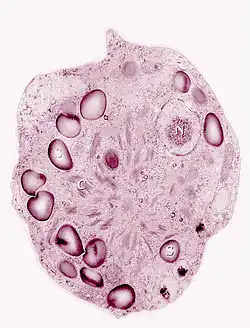

Different taxa of snow algae produce differing amounts of primary and secondary carotenoids, meaning the color of a snow algae bloom can give some indication of the composition of algae found there. The alga Chlamydomonas nivalis is a very abundant component of red blooms due to its high concentrations of astaxanthin and its derivatives.[12] Many Chloromonas species are associated with green or orange-yellow snow due to the primary carotenoids they produce.[13] Similar colors of snow can also vary in composition by region, showing large scale biogeographical trends in the snow algae distribution.[14]

The algae's life stage may also play a large role in the color of the snow. Many blooms are higher in chlorophylls and primary carotenoids during early stages of the bloom, causing the snow to appear green or yellow.[15] Later in the summer, the bloom may switch to orange or red due high production of astaxanthin during low nutrient periods and the snow algae’s more stable cyst stage that they use to over-winter.[16]